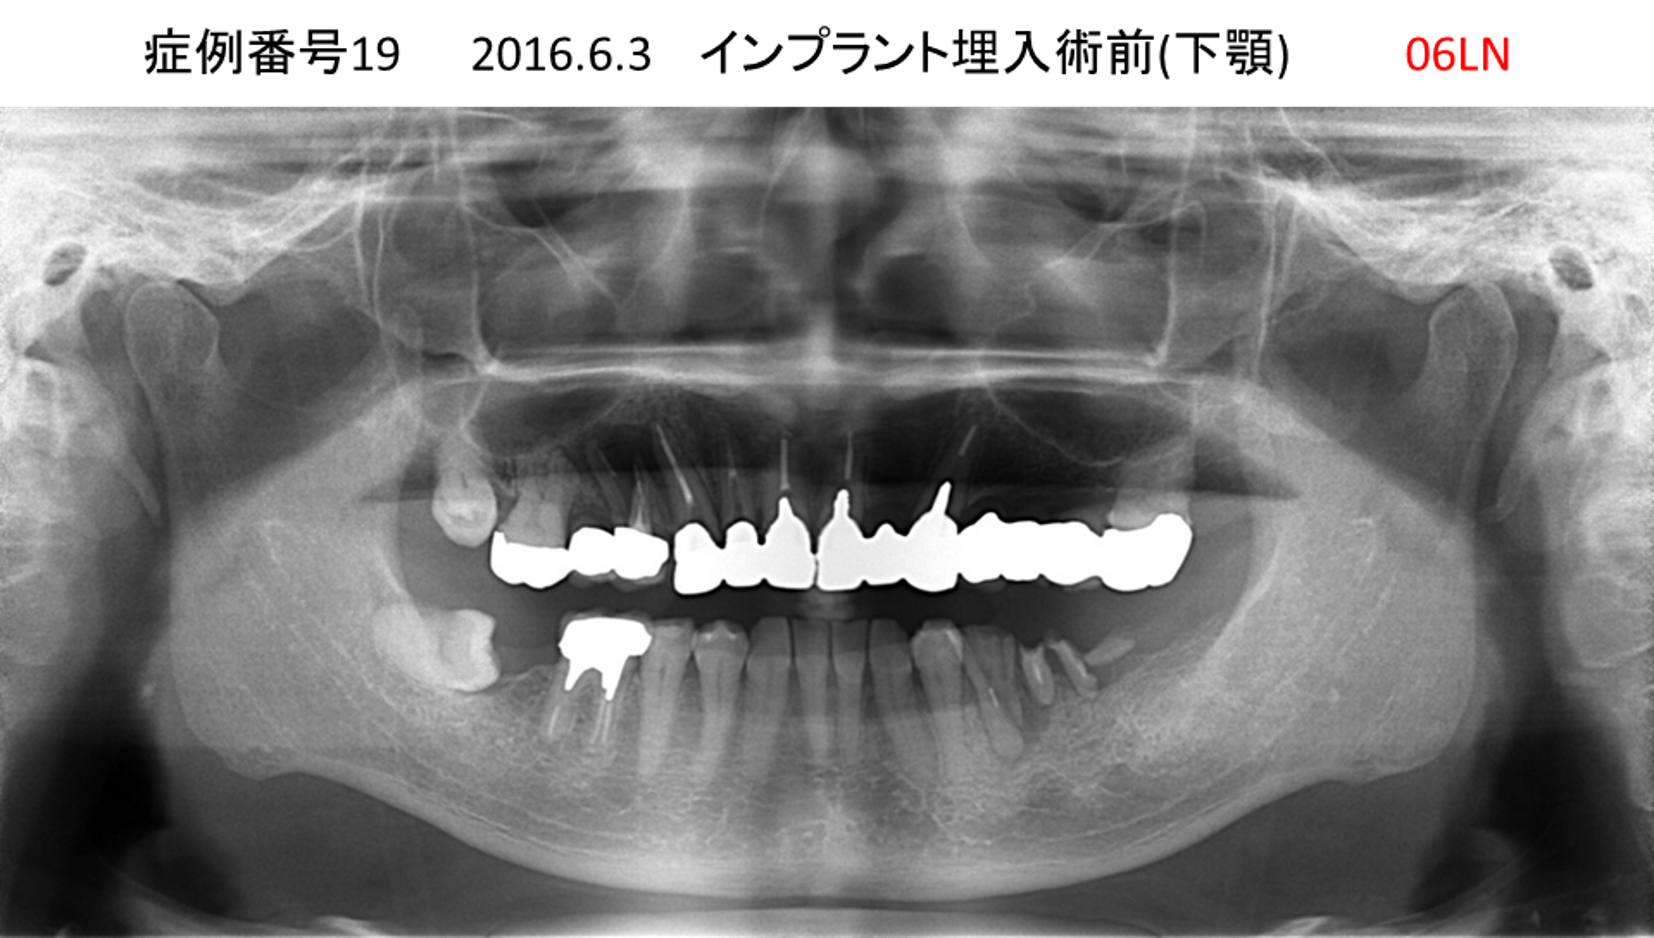

前の歯医者で歯をいっぱい抜かれてしまった患者様のインプラント症例

| 治療名称 |

インプラント |

| 治療費用 |

270万円+税 |

| 治療期間 |

6か月 |

| 患者さんの症状(主訴) |

前の歯医者で歯をいっぱい抜かれてしまった。インプラントをいっぱいやっているところにかかりたかった |

| 治療内容 |

サイナスリフト 抜歯即時インプラント |

| 治療結果 |

特に違和感なく使えている。歯があったときと同じように噛める。 |

| 治療の注意点(リスク/副作用) |

インプラントが壊れたら再治療が必要 |